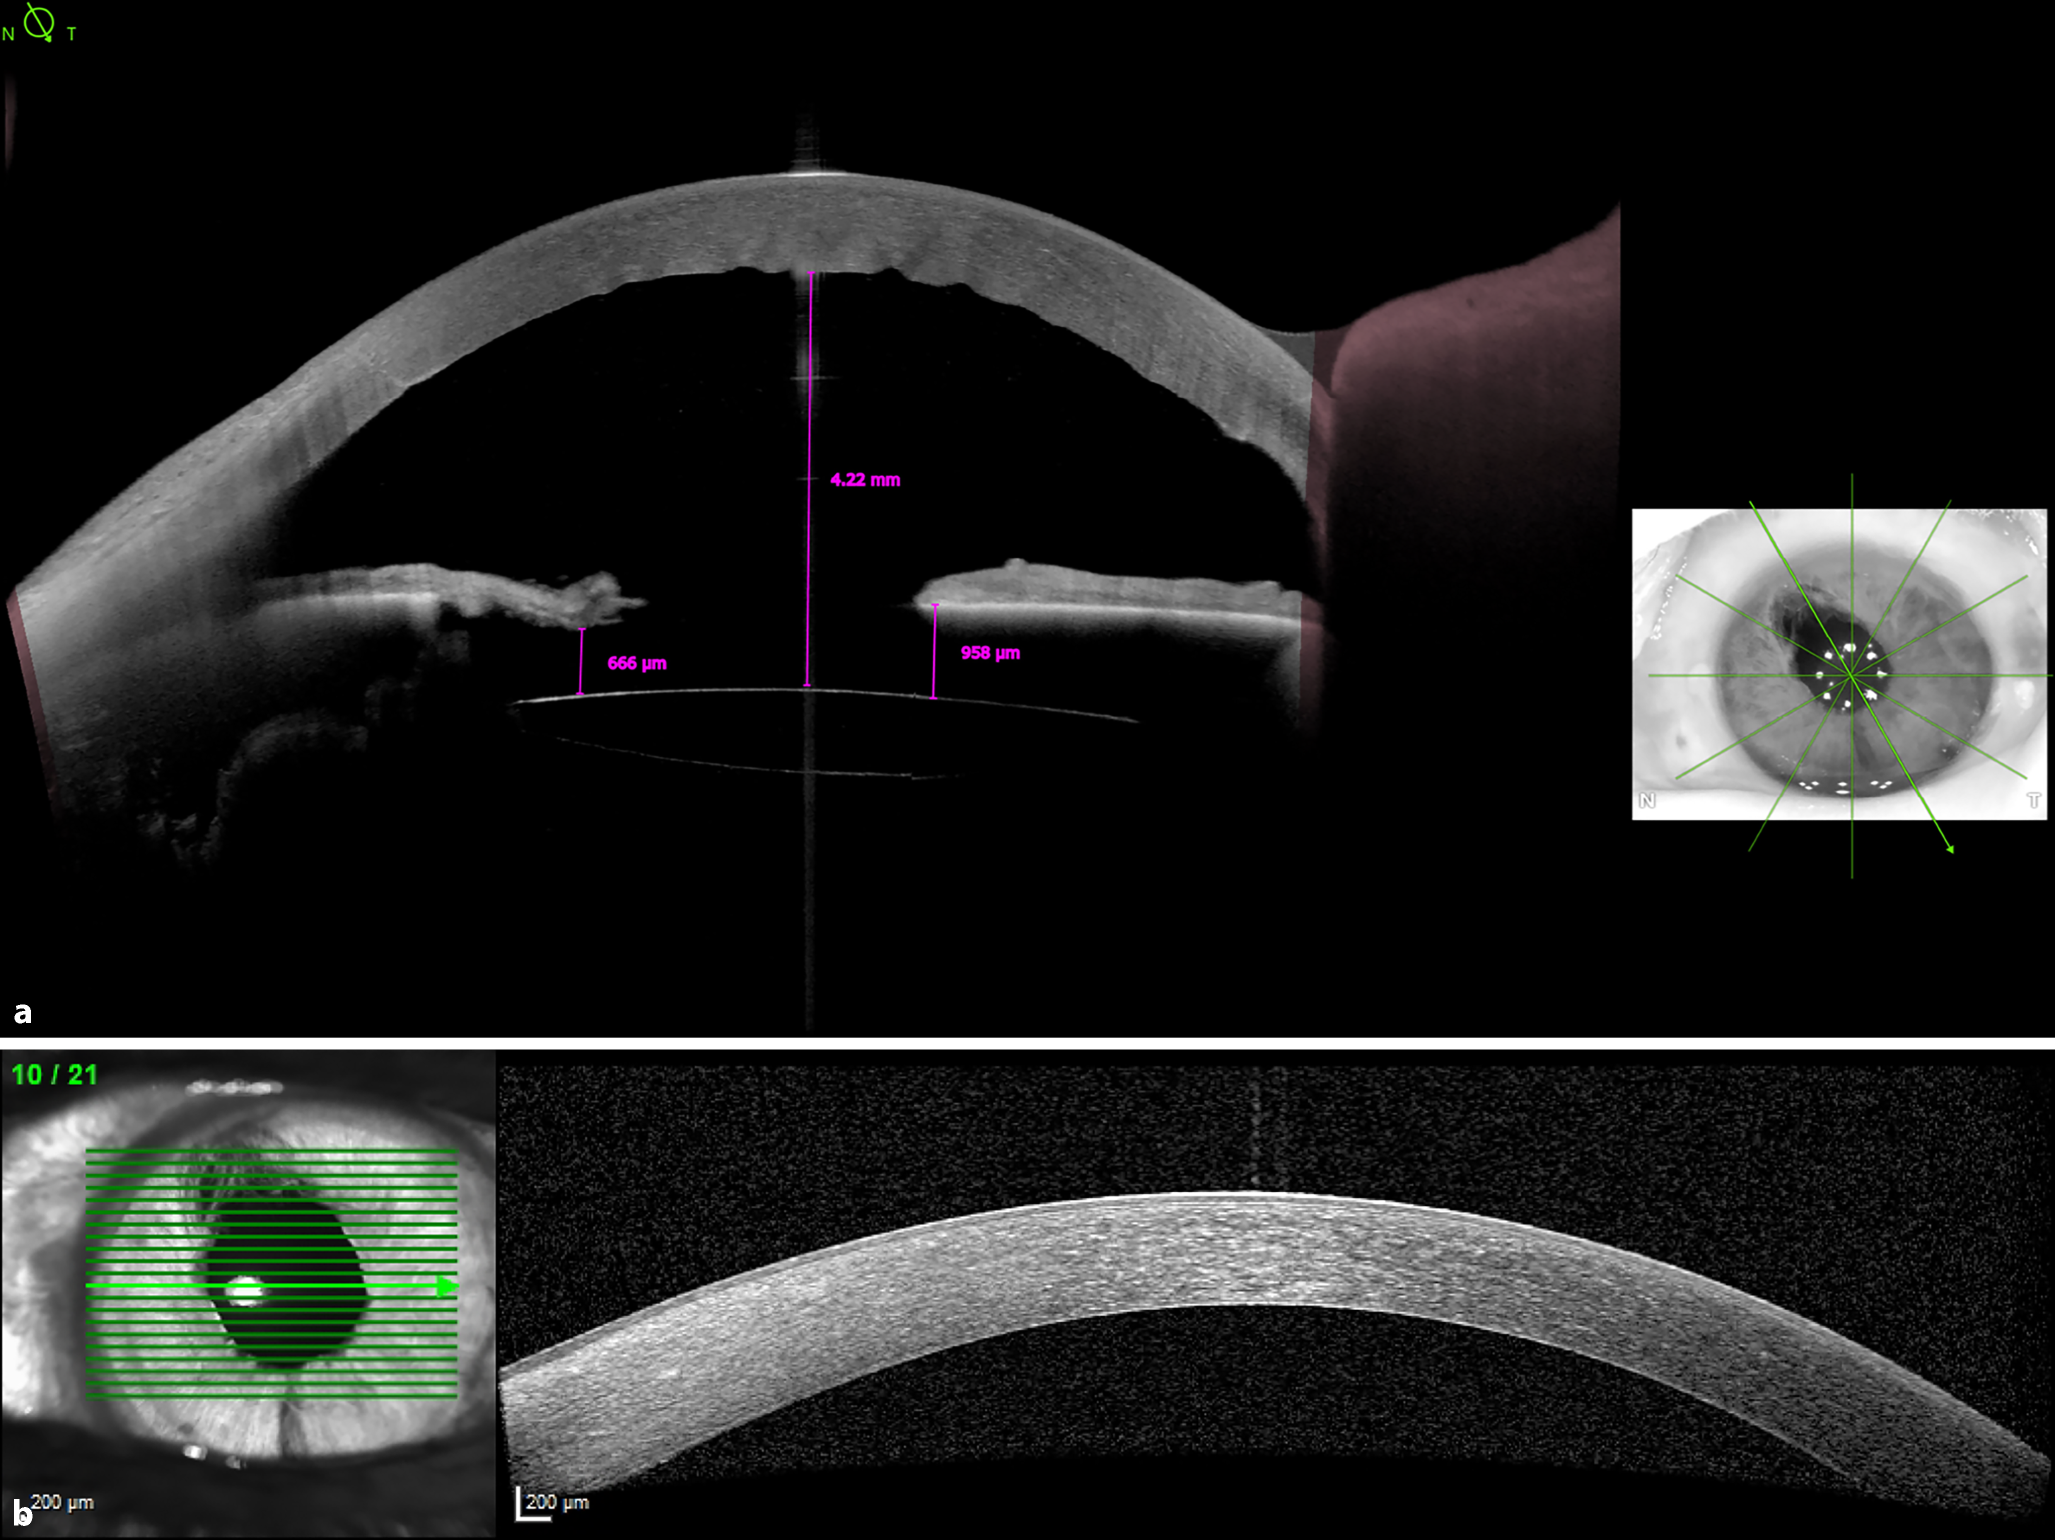

Abb. 3

Vorderabschnitts-OCT: a 1 Tag postoperativ, b 7 Wochen postoperativ

Die Vorderabschnitts-OCT-Untersuchung bestätigte den klinische Befund einer noch ödematösen Hornhaut mit Descemet-Falten (Abb. 3a). Wir vermaßen den Abstand zwischen IOL und Iris, der im Bereich des Irisdefektes bei 11 Uhr 666 µm und bei 5 Uhr 958 µm betrug. Der Abstand zwischen IOL-Vorderfläche und Hornhautrückfläche betrug 4,2 mm.

Zwar ist die Carlevale-IOL mit einem optischen Durchmesser von 6,5 mm und einem Gesamtdurchmesser von 13,2 mm insgesamt größer als andere Sekundärlinsen [1]. Eine Dislokation des 6 mm langen und 0,46 mm dicken Ozurdex-Implantats durch die seitlichen Teile der Linsenhaptik oder superior und inferior der Linsenoptik ist jedoch durchaus möglich, wie dieser Fall zeigt. Der von uns gemessene Iris-Linsen-Abstand liegt im Bereich der bei anderen IOLs erhobenen Werte [7] und schafft ebenfalls Raum für das Luxieren des schmaleren Ozurdex-Implantats.